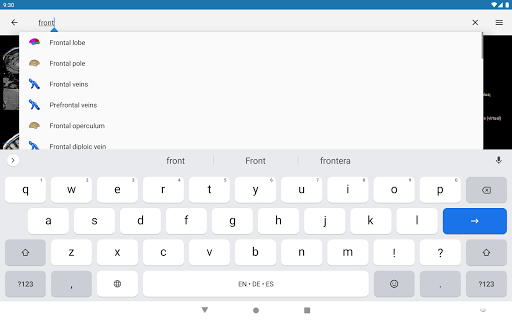

- Localice fácilmente las estructuras anatómicas gracias a la búsqueda de índice

*Encuentre sus partes anatómicas más fácilmente gracias a la nueva función de búsqueda, más intuitiva y poderosa.